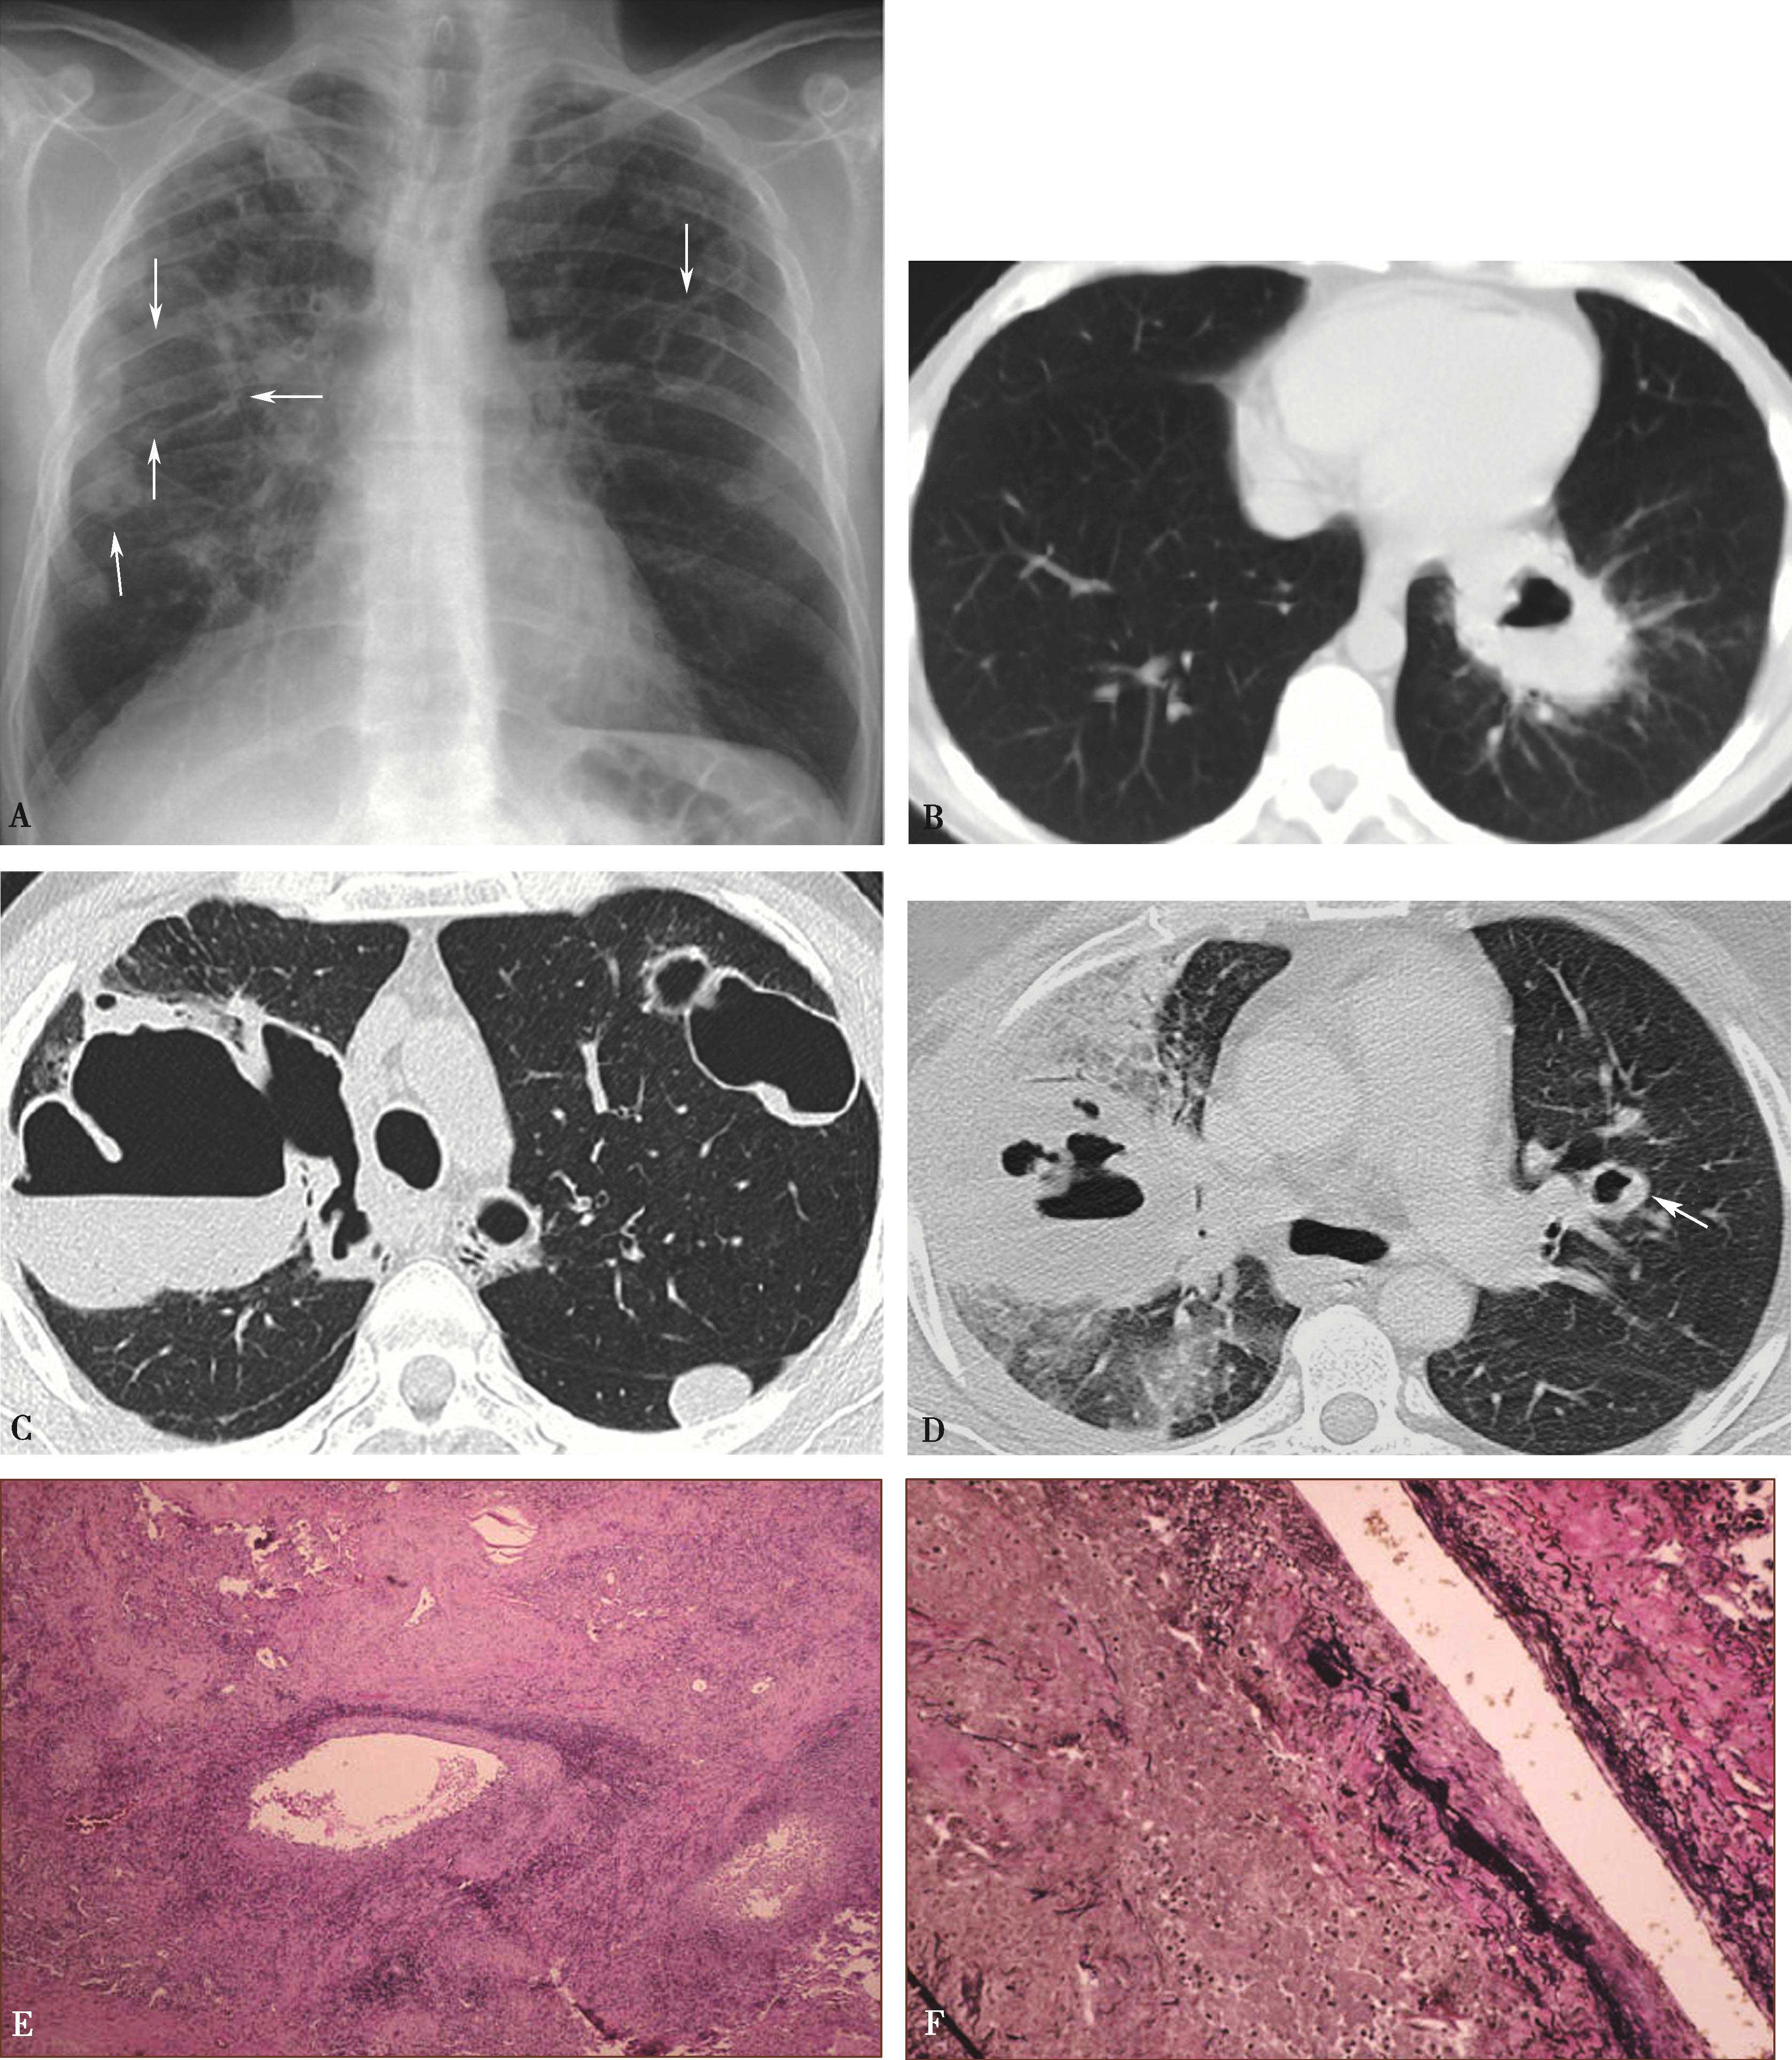

高分辨率CT(平扫)对诊断有重要价值。显示肺实质多发性斑片状、大小不等结节及空洞形成,主要分布两肺中下野,多发性/多样性(不规则,多发,大小不等)为其特点,并存胸膜反应,胸腔积液(图8-5-6)。

图8-5-6 坏死性肉芽肿性血管炎(韦格纳肉芽肿)

A.胸部X线片,两肺多发结节,不规则空洞形成(↑);B~D.横断图像,两上、下肺多发不规则结节肿块,大小不等,不规则空洞形成,壁薄厚不一,边缘不规则,液平形成;病理检查:E.肺小血管横断面,显示炎性细胞浸润累及部分血管;F.肺小血管纵切面,炎性细胞浸润,部分管壁破坏。CT诊断:韦格纳肉芽肿(病理证实为坏死性肉芽肿性血管炎)

(2)坏死性肉芽肿性肺血管炎(韦格纳肉芽肿):

在临床上常被误诊,为了能早期诊断,对有以下情况者应反复进行活组织检查:不明原因的发热伴有呼吸道症状;慢性鼻炎及副鼻窦炎,经检查有黏膜糜烂或肉芽组织增生;眼、口腔黏膜有溃疡、坏死或肉芽肿;肺内有可变性结节状阴影或空洞;皮肤有紫癜、结节、坏死和溃疡等。确诊依据病理组织学检查。